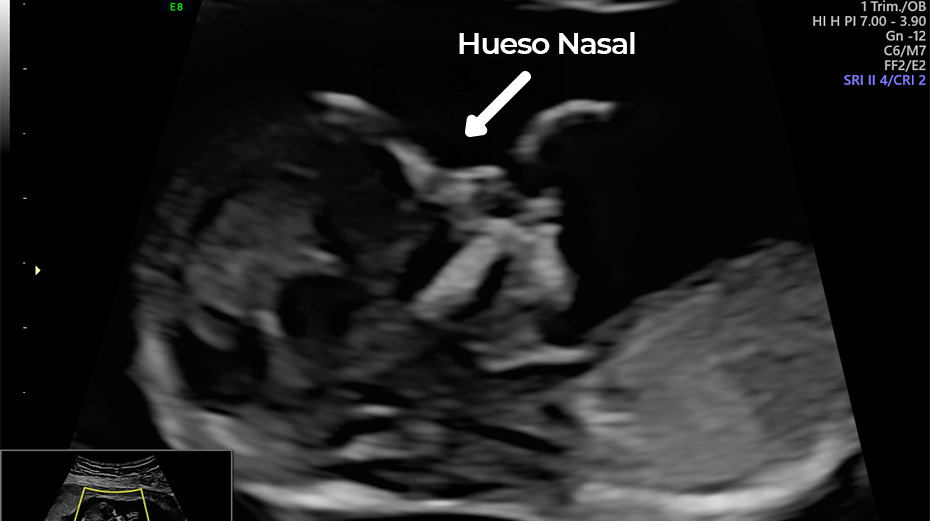

Desde la semana 11, realizamos estudios clave para detectar síndrome de Down, ausencia de hueso nasal o anomalías en la translucencia nucal.

Este estudio se realiza en el primer trimestre y es clave para detectar posibles alteraciones cromosómicas como síndrome de Down, trisomía 18 y trisomía 13.

Se evalúan marcadores como:

• Hueso Nasal

Translucencia Nucal Ductus Venoso Hueso Nasal Frecuencia Cardiaca Fetal